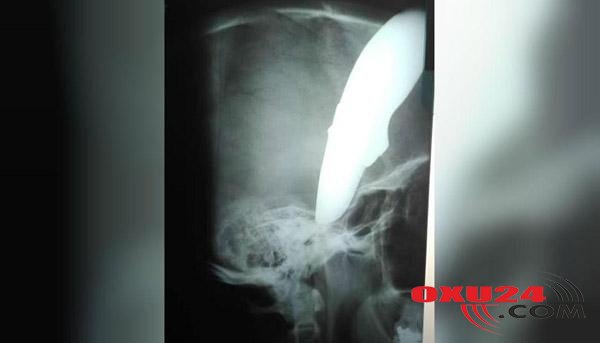

Oxu24.com xəbər verir ki, Şaun Veyn adlı velosipedçi iki naməlum şəxsin silahlı hücumuna məruz qalıb. Soyğun törətmək istəyən naməlum şəxslər 34 yaşlı şəhər sakininin başına bıçaq saplayıblar. O, isə ən yaxın xəstəxanaya piyada gedib. Başına 15 sm uzunluğunda bıçaq saplanan şəxsi görənlər qorxu və təəccübdən yerlərində donub qalıblar. Onun sakit şəkildə “boş həkim varmı?” sözləri isə bu təəccübə duz-bibər olub.Yaralı dərhal əməliyyat edilib və möcüzəvi şəkildə sağ qalıb.\"\"